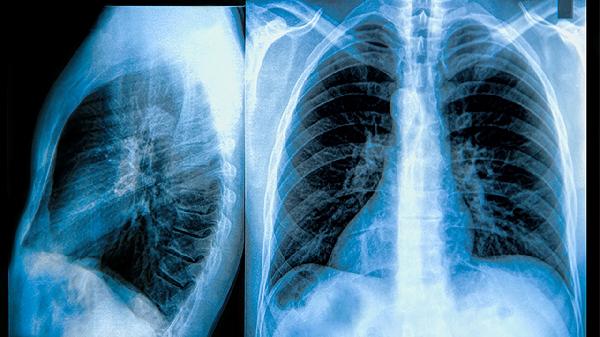

肺钙化灶什么意思

肺钙化灶是指肺部组织中出现钙盐沉积形成的病灶,常见于炎症、感染或结核等疾病后遗症,通常无需特殊治疗,但需定期随访观察。肺钙化灶的形成可能与肺部感染、结核、炎症或肿瘤等病理过程有关,具体原因需结合影像学检查及病史综合判断。对于无症状的肺钙化灶,一般无需干预,定期复查胸部CT即可;若伴随咳嗽、胸痛等症状,需进一步检查排除其他疾病,如结核活动期或肿瘤等,必要时进行抗结核治疗或手术切除。